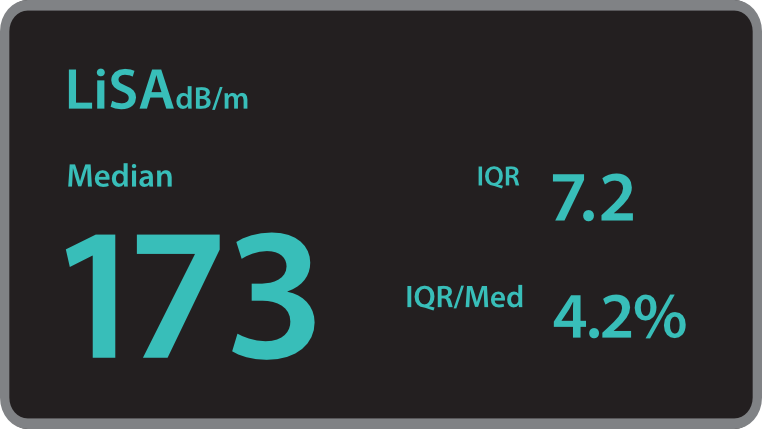

? ??? ?? ???? ???? ?? ???? Hepatus? ? ??? ??? ???? ??? ??? ?????. ???? ????? ??? ? ?? ??? ???? ????? ? ?? ???? ? ?? ??? ??? ??? ?????.

???? ?? ?? ??

??? ???? ?? ? ??? ? ? ???? ?? ??, ??, ???? ? ?? ??? ??? ? ????. ?? ?? ???? ?????.